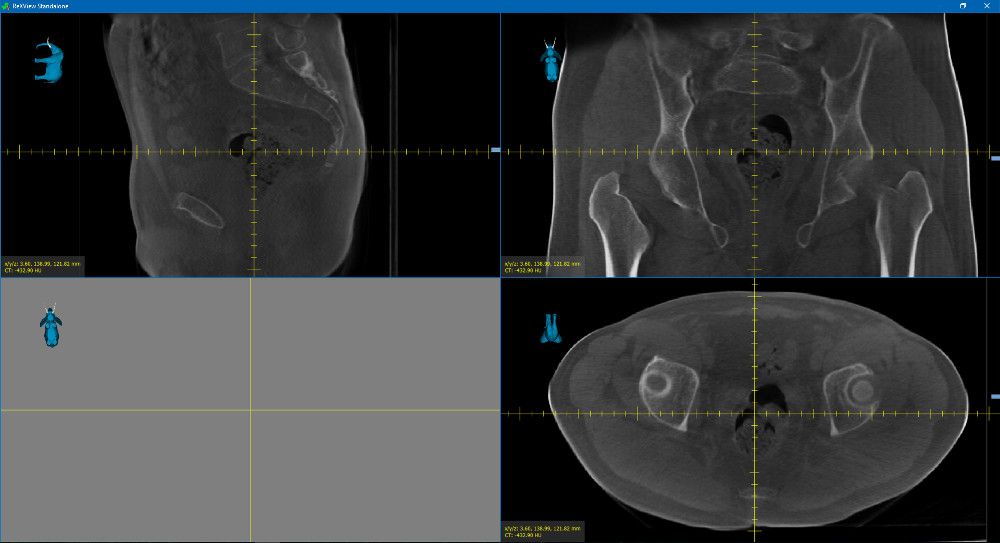

Gemeinsam mit MedPhoton haben wir ReXView (Reconstruction und X-ray Viewer) entwickelt. ReXView ermöglicht die Visualisierung und den Vergleich volumetrischer 3D-Daten und 2D-Projektdaten.

Mit Hilfe verschiedener Messwerkzeuge ist es möglich, Bilddaten präzise zu analysieren. Zusätzlich können Bilder mit 3D-Objekten (zum Beispiel inneren Organen) überlagert werden. Dadurch ermöglicht ReXViewer eine detaillierte Diagnose der Patientendaten, die von geschulten Radiologen erstellt werden kann.